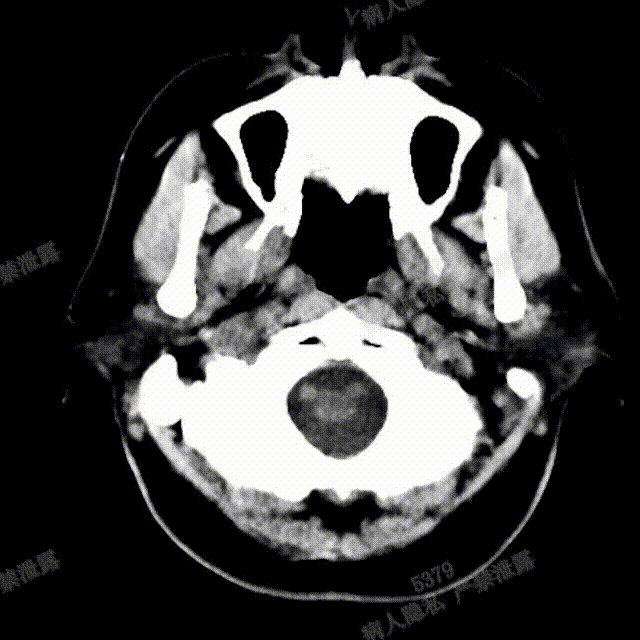

完全释放FRED 5514血流导向密网支架,正、侧位造影及术后CT复查结果观察,载瘤动脉通畅、支架贴壁良好、动脉瘤内造影剂滞留、颅内未见明显异常。

正、侧位造影及术后CT复查结果观察,载瘤动脉通畅、支架贴壁良好、动脉瘤内造影剂滞留、颅内未见明显异常。